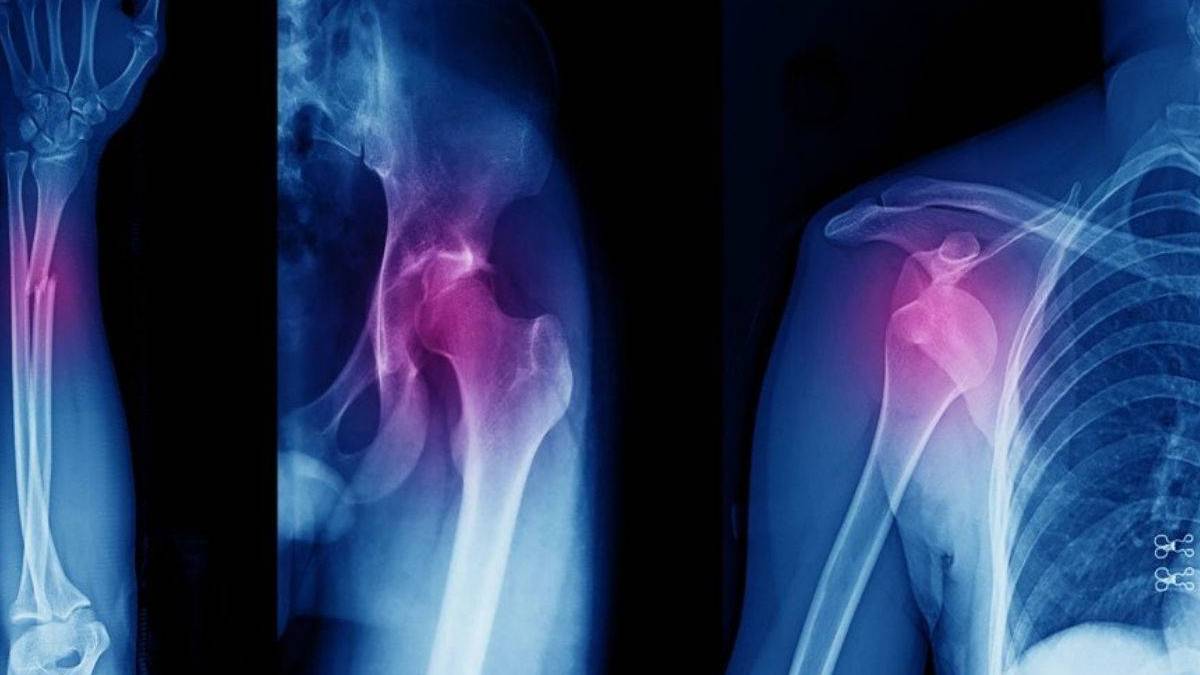

Güney Kore’deki Sungkyunkwan Üniversitesi’nden araştırmacılar, kırık kemiklerin tedavisinde devrim yaratabilecek yeni bir teknoloji geliştirdi. Özel tasarlanmış bir ısı tabancasıyla çalışan bu sistem, ameliyat sırasında 3D baskı yöntemiyle kemik grefti üreterek kırıkların doğrudan onarılmasını sağlıyor.